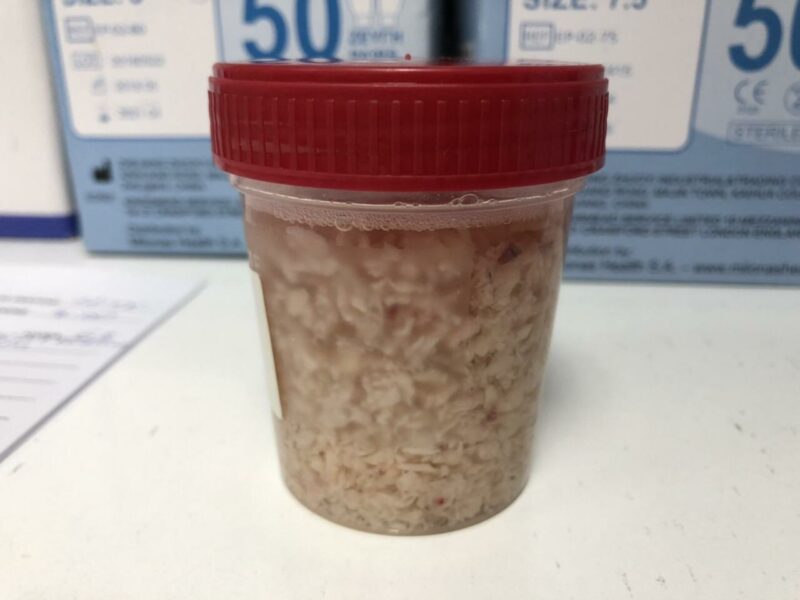

- το αδένωμα τεμαχίζεται και αφαιρείται με τη βοήθεια του morcellator το οποίο εισάγεται μέσα από τον αυλό του ενδοσκοπίου (εικόνες 7-9)

- οι λεπίδες του morcellator τεμαχίζουν το προστατικό αδένωμα και τα κομμάτια αφαιρούνται με τη βοήθεια αντλίας με αρνητική πίεση

εικόνες 7-9

εικόνα 10

Εικόνα 11. Όγκος προστατικού αδενώματος που αφαιρέθηκε με εκπυρήνιση